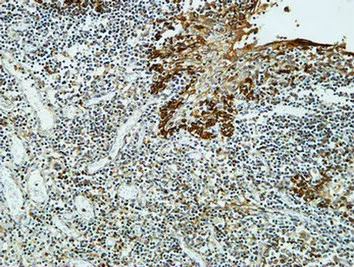

HDC Rabbit Polyclonal Antibody

Cat: APRab11956

Size1:50μl Price1:$118

Size2:100μl Price2:$220

Size3:500μl Price3:$980